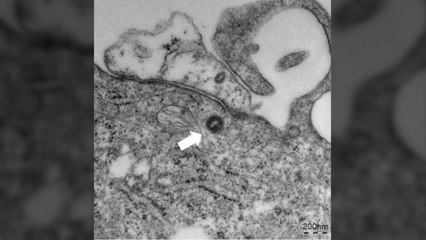

국내 지역사회 감염으로 추정되는 엠폭스 환자가 10명 더 확인됐습니다. br br 주말 사이 처음으로 두 자릿수 확진자 증가를 기록한 데 대해 방역당국은 현재 역량으로 관리 가능하다면서 증상이 있는 경우 적극 검사를 받으라고 당부했습니다. br br 기정훈 기자가 보도합니다. br br [기자] br 주말 사이 엠폭스 환자가 한꺼번에 10명이나 더 늘었습니다. br br 지금까지 누적 30명입니다. br br 지난주 목요일 발표 이후 나흘 만이긴 하지만 한 번에 두 자릿수 확진자 발표는 처음입니다. br br 금요일과 토요일 각각 4명씩, 일요일에 2명이 확진됐는데, 거주지는 서울이 6명으로 가장 많고, 경기 3명, 경북 1명입니다. br br 10명 모두 3주 안에 해외에 다녀온 적이 없고 위험에 노출된 적은 있어서, 국내 감염으로 파악됩니다. br br 대부분 통증을 동반한 피부병변이 있었고 모든 환자가 발진이 있었습니다. br br 이달 들어 꾸준하게 늘고 있지만, 감염 경로가 제한돼 있어 무차별 확산 우려는 크기 않습니다. br br 누적 확진 30명 가운데 27명이 밀접 접촉 감염. br br 즉 피부 접촉이나 성 접촉이 있었다는 얘깁니다. br br 나머지는 환자 접촉 감염 2건, 의료진이 주사침에 찔려 감염된 것 1건 뿐입니다. br br 세계보건기구(WHO)는 지난해 "엠폭스는 제한된 감염경로로 인해 관리가 가능한 질병" 이라고 안내했습니다. br br ## br br 우리 방역당국도 현재 대응 역량으로 충분히 관리 가능하다며, 크게 우려할 필요가 없다는 입장입니다. br br 밀접 접촉으로 전파되는 특성 때문에 코로나19나 메르스처럼 전파될 우려는 적다고 강조합니다. br br [인터뷰 : 이형민 질병관리청 신종감염병대응과장] br br "질병 속성상 통상의 많은 국민에게 만연해 있다기보다는 위험도가 높은 그런 상황에 노출되어 계신 분들 이런 분들 내에서 제한적으로 전파가 될 거라고 그렇게 보고 있습니다. br br 다만 개인 신상의 노출 우려 때문에 숨은 환자가 많을 수 있다는 지적에 대해서는 br br 확진자는 물론 검사를 문의하는 사람에 대해서도 철저하게 개인 정보를 보호하고 있다면서 의심이 되면 주저하지 말고 보건소 등 의료기관을 찾아 진료를 받으라고 당부했습니다. br br YTN 기정훈입니다. br br br br br br br YTN 기정훈 (prodi@ytn.co.kr)br br ※ '당신의 제보가 뉴스가 됩니다' br [카카오톡] YTN 검색해 채널 추가 br [전화] 02-398-8585 br [메일] social@ytn.co.krbr br ▶ 기사 원문 : ▶ 제보 안내 : , 모바일앱, social@ytn.co.